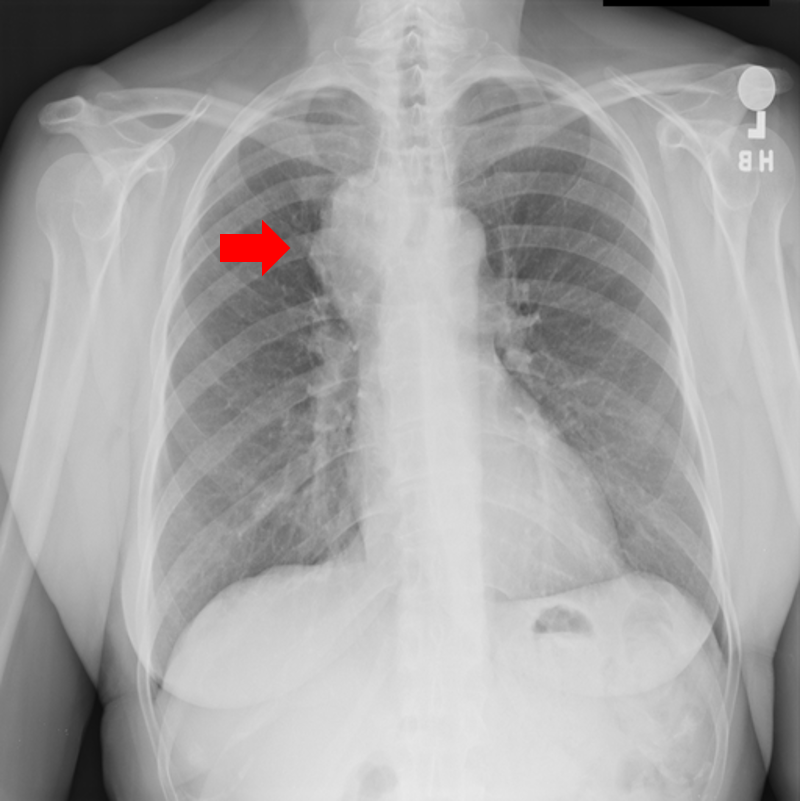

Figure 9: Typical CXRs with pneumonia-like lung opacity from among the top 1,000 CXRs most likely to have an abnormality according to the logarithm posterior probability out of the 13,863 abnormal CXRs. The lesion is indicated with a red arrow if applicable.

Figure 9 shows CXRs suggested to have pneumonia-like lung opacity with the logarithm posterior probability. These CXRs are the top 1,000 CXRs most likely to have an abnormality out of the 13,863 abnormal CXRs.